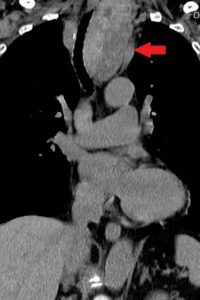

觸診為腹股溝疝氣的主要診斷方式,必要時才會以超音波及電腦斷層輔助判定嚴重程度。修補方式有直接將周圍組織縫合以及覆蓋人工網膜兩種方式,可透過傳統手術、腹腔鏡微創手術與達文西微創手術執行,但相較於組織縫合可能導致張力過強、容易復發,人工網膜疝氣修補可減少組織張力,且相比於單純縫合,網膜能提供額外的支撐與強度,減少疝氣口的張力與擴大補強範圍;且對於復發性疝氣、大型疝氣或腹壁疝氣,單純縫合常無法有效修補,而網膜則能提供額外支撐,提升手術成功率。以林先生為例,由於第一次手術的醫師是在緊急情況之下也做了壞死腸段切除,因此可能有感染疑慮,所以沒有使用人工網膜修補,加上術後復發且出現雙側腹股溝疝氣,腹腔鏡手術的傷口位置以及視野、空間都較為受限,達文西手術就成為優先選擇。陳昱天醫師說明,達文西手術優勢在於視野清晰、機械手臂靈敏,可以精確修補疝氣缺口,從而有效降低手術風險並提高患者康復速度與預後效果。